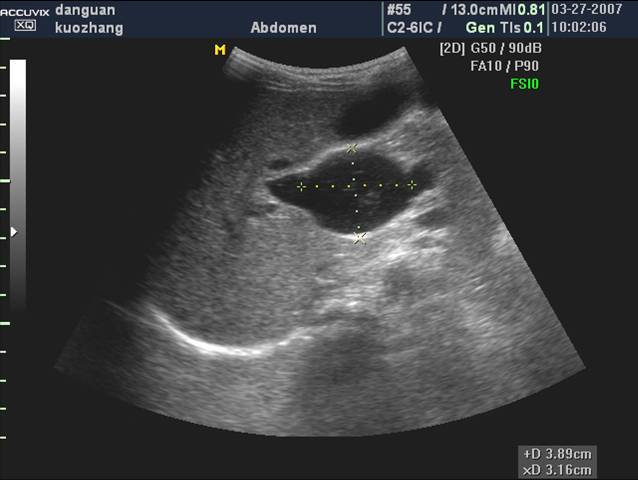

1 胆管结石